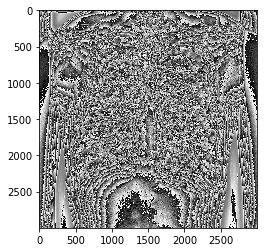

単純に8bitに変換してみます。

# numpyで8 bit変換してみる

np_img = pixels.astype('uint8')

plt.imshow(np_img,cmap="gray")

plt.show()

違うなあ。